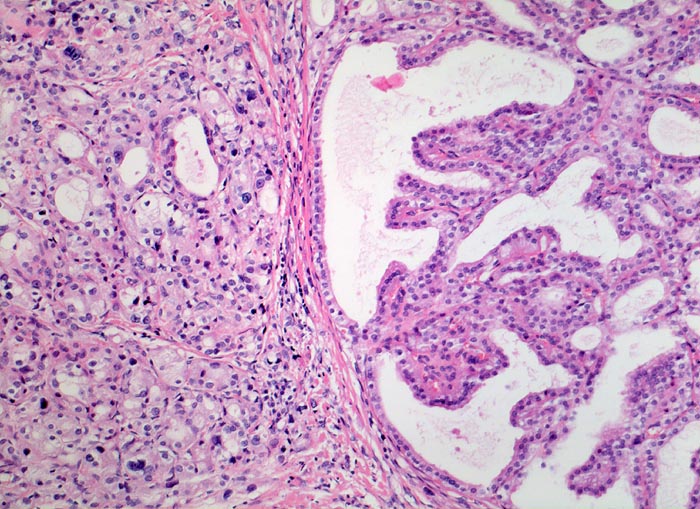

Regeneratknoten bei Morbus Basedow

Kleintubuläre und solide Parenchymanteile, sowie kleine kolloidfreie Follikel mit ausgeprägter Kernpolymorphie bei reichlich vorhandenem hellem Zytoplasma. Ausserdem ein Regeneratknoten mit pseudopapillären Formationen (Follikel im Papillenstroma, die Zytomorphologie entspricht nicht einem papillären Karzinom) rechts im Bild.

Zusätzliche Zeichen einer Hashimoto Thyreoiditis (ausgedehnte Parenchymvernarbung)

Vor 2 Jahren beidseitige Strumektomie. Exophthalmus und Myxödeme der Unterschenkel.